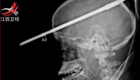

男孩被鱼叉戳穿脑颅 奇迹存活